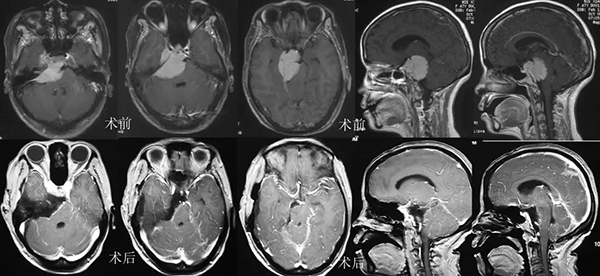

垂体瘤术前影像

颅咽管瘤术前影像

岩斜脑膜瘤手术前后

枕骨大孔脑膜瘤手术前后